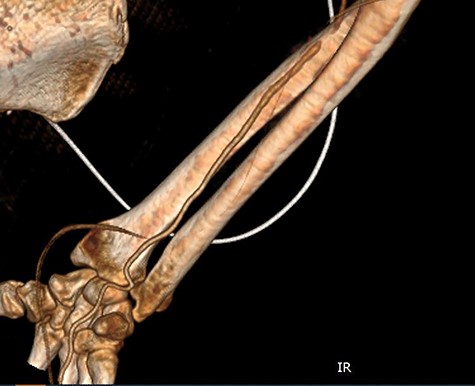

Seven days later, while his general condition was deteriorating, he developed acute ischemia in his right thumb and index finger (Fig. 2). In the ipsilateral forearm, a radial artery catheter had been inserted for monitoring. An urgent radial artery embolectomy was performed and restored the arterial supply to the right hand. The antithrombotic agent was changed to fondaparinux (7.5 mg/once daily). However, within the next few days, it was clinically evident that the revascularization effort was unsuccessful as the thumb and index finger developed dry gangrene. On examination, there was no palpable radial pulse, the ulnar artery pulse was palpable at the level of the wrist and the capillary refill time was normal at the middle, ring and little fingers. A CT angiography (Figs 3 and 4) was performed, demonstrating complete thrombosis of the radial artery beginning at the level of the elbow as well as a 70% occlusion of the ulnar artery ~15 cm proximal to the wrist. Thrombosis of the right axillary vein was also seen (Fig. 5). Orthopedic review was requested for consideration for finger amputation with a recommendation for arm amputation at the level of the elbow. Unfortunately, the patient died 72 h later from respiratory failure following a 24-day admission in ICU.

Multiplanar reformation image shows severe near occlusion 6-mm stenosis of the ulnar artery.